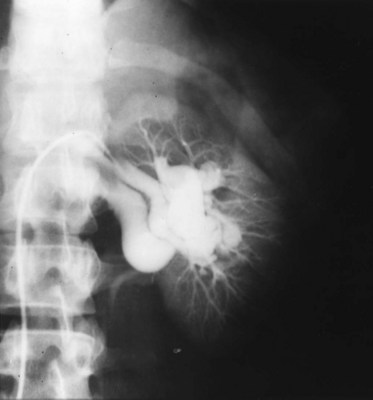

Renal arteriovenous fistulas are relatively uncommon lesions that are generally discovered during the course of angiographic evaluation for suspected renal or renovascular disease. There are three categories of renal arteriovenous fistulas: congenital, idiopathic, and acquired (Tynes et al, 1970; Novick, 1982).

Congenital fistulas have a cirsoid or angiomatous configuration with multiple communications between arteries and veins. They are usually supplied by a renal arterial branch of normal caliber. The angiographic appearance is one of multiple, small, interconnecting arterial and venous channels with impaired distal renal parenchymal vascularity and early filling of the renal vein. They constitute 22% to 25% of all renal arteriovenous fistulas, occur equally in both sexes, and generally do not become manifest until adult life.

Idiopathic fistulas are single, are not cirsoid, and have no apparent cause. They constitute only 3% to 5% of all renal arteriovenous fistulas. These lesions are called idiopathic because their angiographic appearance is similar to that of acquired arteriovenous fistulas, but their origin is unclear.

Acquired fistulas are the most common type, accounting for 70% to 75% of all renal arteriovenous fistulas. On angiography, they appear as solitary communications between an artery and a vein. By far the most common cause is iatrogenic trauma resulting from needle biopsy of the kidney (Fig. 39–18). Other causes include renal carcinoma, blunt or penetrating renal trauma, inflammation, and renal surgery such as nephrectomy, partial nephrectomy, or nephrolithotomy.

Figure 39–18 Left renal arteriogram shows renal arteriovenous fistula with early filling of the renal vein. This patient had previously undergone needle biopsy of the left kidney.